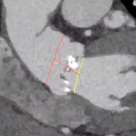

福建医科大学附属协和医院心脏大血管外科邱罕凡教授分享了一例主动脉瘤术后伴极重度横位心的TAVI治疗病例。患者为69岁男性,综合检查资料,为Type1型二叶瓣,L-R融合极重度钙化(钙化积分 1380)、横位心(74.5度),主要在瓣叶边缘及融合脊和无冠窦底,钙化位置预估对人工瓣膜形态影响较大,存在根部损伤、瓣膜移位及瓣周漏风险,术前CT同时发现人工血管存在一处明显折痕,术中需注意避开折痕影响。考虑进行Downsize高位释放,计划植入VitaFlow®27mm瓣膜。

图片

人工血管升主动脉处可见明显折痕